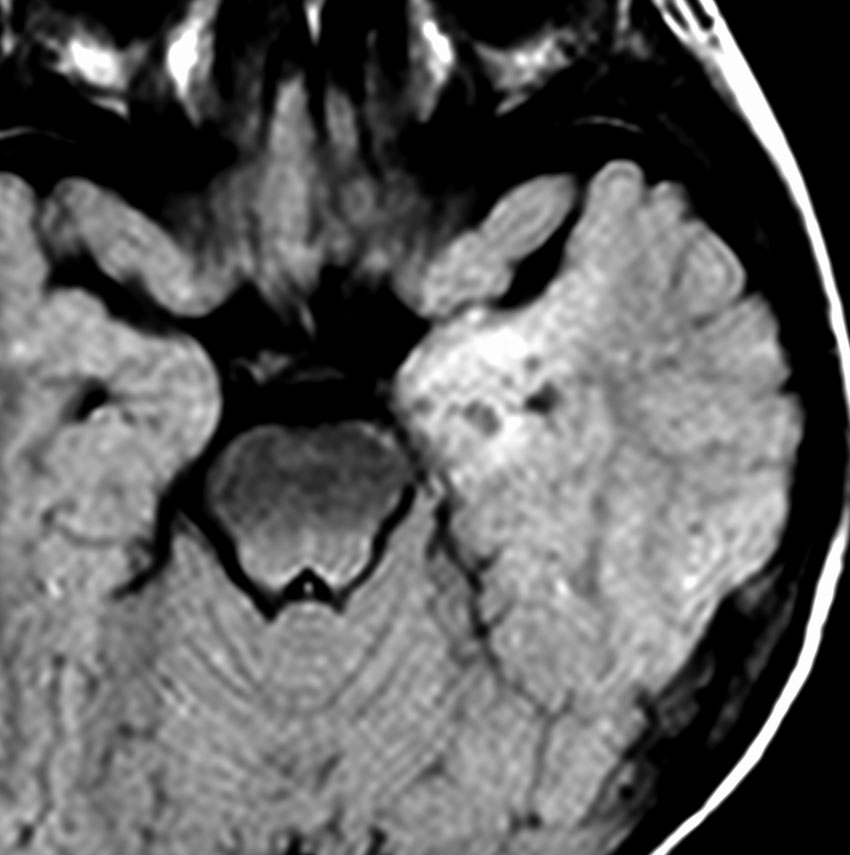

右側頭葉先端の腫瘍です。発症時にはMRIで異常所見がありませんでしたが,徐々に顕在化しました。ガドリニウム増強はなく一部のう胞性です。

4歳時に意識現存を伴う発作が1日3回くらいあるという難治性部分てんかんで発症しました。手術中の頭蓋内脳波で,下側頭回に激しい棘波と棘律動を認め,扁桃体への刺入電極でも棘波がありました。周辺脳にも棘波はありましたが,病変(腫瘍)と扁桃体を切除するのみの手術を行いました (lesionectomy and amygdalectomy)。手術後13年が経過しますが発作はありません。病理では,腫瘍組織内に神経節細胞はなく,皮質異形成 cortical dysplasiaあるいはグリオーマ様病変 gliomatous lesionという診断でした。1p/19qに欠失はありませんでしたが,乏突起膠腫も否定できない周囲灰白質に浸潤性の腫瘍でした。この例はlow-grade gliomaでしょうが確定病理診断はできないものです。どちらであっても,基本的にグレード1ですから,手術後再発はしません。